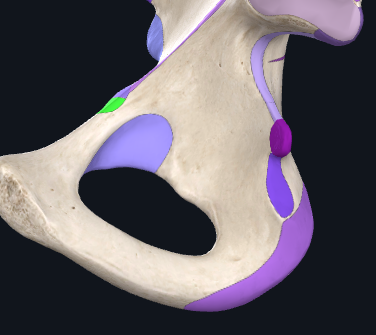

Articulations of the hip bone

Sacrum and ilium - to form sacroiliac joint.

Pubes - to form pubic symphysis

Acetabulum and femur - to form hip joint

What three bones make up the hip bone?

1) Ilium - largest bone of the three

2) Ischium - sits inferiorly to the ilium

3) Pubis - inferiormedially to the ilium

These bones join at the tri-radiate cartilage that is found in the acetabulum. This cartilage fuses at around 15-17yo.